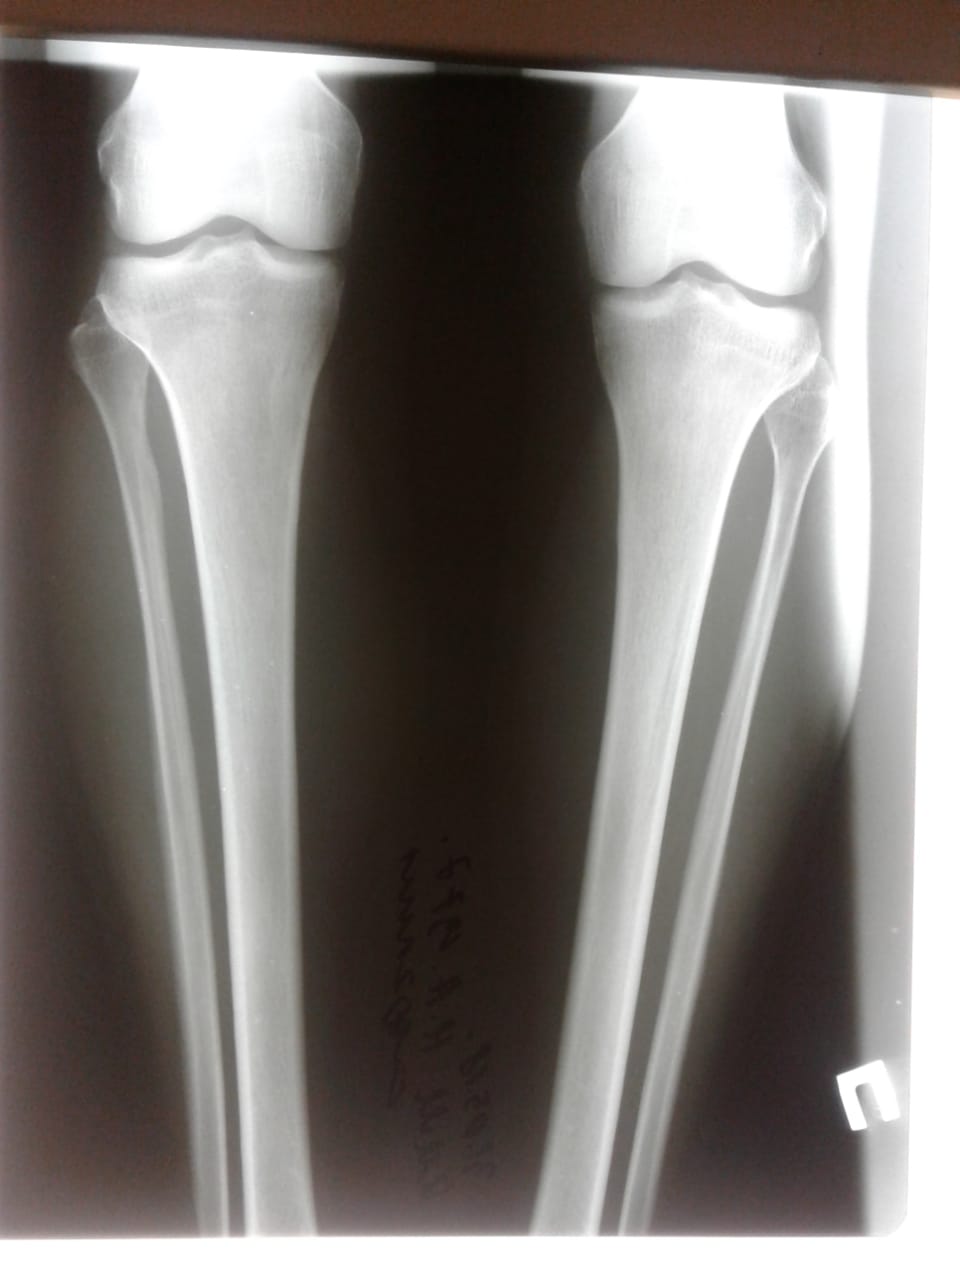

23 день после операции.

Вот в чем суть, щадящей и малотравматичной методики доктора Онипко.